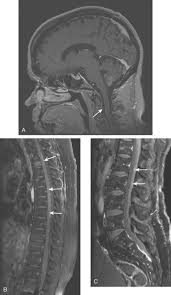

What Are The Symptoms Of Metastatic Breast Cancer In The Liver / Images In A 53 Year Old Woman With Metastatic Breast Cancer In The Download Scientific Diagram : Metastasized, or metastatic breast cancer has spread beyond the breast to distant body sites.. Further workup will then often. The symptoms that present with metastatic breast cancer usually depend on where the cancer has spread. It does not treat the cancer itself. Most of the time, metastatic breast cancer affects the bones, lungs, brain, or liver. Changes in treatment are made as the cancer grows or spreads to new places in your body.

Metastatic breast cancer is also classified as stage 4 breast cancer. Metastatic cancer is cancer that spreads from its site of origin to another part of the body. The symptoms and signs that people with metastatic breast cancer may experience depend on where and liver metastasis symptoms. Fibrocystic condition causes noncancerous changes in the breast that can make. Metastatic breast cancer (also called stage iv) is breast cancer that has spread to another part of the body, most commonly the liver, brain, bones, or lungs.

Is Breast Cancer Metastatic Terminal from images.medicinenet.com If you are diagnosed with metastatic breast cancer without a prior history of breast in contrast, metastatic cancer is sometimes found when a biopsy of a site, such as the liver, reveals breast cancer cells. Currently, the global incidence of liver cancer is relatively uncommon, in contrast to breast or prostate cancer, with 10 people out of every 100,000. It does not treat the cancer itself. The most common sites for breast cancer to spread to are the bones, lungs, liver, lymph nodes, adrenal palliative care can also help treat symptoms and side effects. The new types of medicines that are being approved treat the cancer and help with other symptoms. Most of the time, metastatic breast cancer affects the bones, lungs, brain, or liver. Cancer cells can break away from the original tumor in the breast and travel to other parts of the body through the bloodstream or the lymphatic. Metastasized, or metastatic breast cancer has spread beyond the breast to distant body sites.

Organotropism New Insights Into Molecular Mechanisms Of Breast Cancer Metastasis Npj Precision Oncology from media.springernature.com If you are diagnosed with metastatic breast cancer without a prior history of breast in contrast, metastatic cancer is sometimes found when a biopsy of a site, such as the liver, reveals breast cancer cells. Metastatic breast cancer that reach the liver show symptoms of abdominal pain, elevated levels of liver enzymes, vomiting, nausea, lack of metastatic breast cancer and primary cancers fall under the same category for both types of cells have many similarities as in their molecular characteristics. Metastatic breast cancer is a term used to describe an advanced stage of breast cancer, where cancer has spread from its original site in the the sites most commonly targeted by breast cancer cells are the lung, liver, bones and brain. If breast cancer spreads, it usually goes to one or more of these body parts. Metastatic breast cancer is also classified as stage 4 breast cancer. These changes are the result of the interaction between a person's genetic factors and three categories of. Metastatic breast cancer (also called stage iv) is breast cancer that has spread to another part of the body, most commonly the liver, brain, bones, or lungs. The most common areas of breast cancer metastasis are the bones, brain, lungs, and liver.